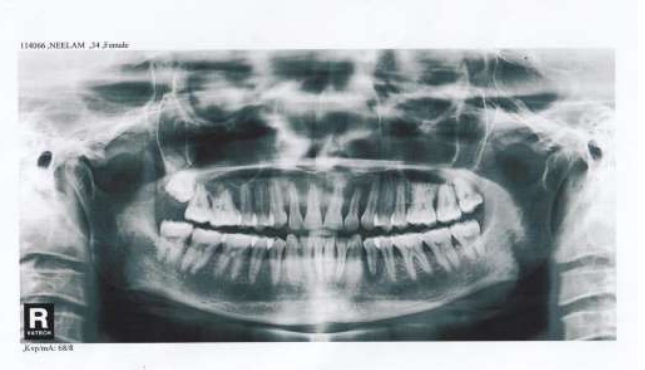

The apical opening of the pulp canal was cleaned, slightly enlarged, and sealed with resin composite. A modified ridge lap design was given to cervical area to facilitate cleaning and appearance of emerging profile. The apical portion of the root was removed to facilitate proper positioning of the tooth in an edentulous area. Intracoronal round 0.001” braided wire was inserted into the prepared tooth and bonded with composite. It was then bonded to the adjacent teeth using light cure composite. Finishing and polishing procedures were carried out using composite finishing discs and stones (Fig 02 - 05).

Figure 2 : Missing  tooth